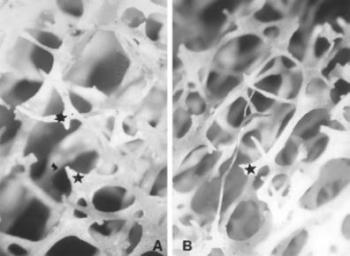

47. ábra. Részlegesen resorbeálódott csontgerenda (csillag) ágyéki csigolyában. 12. század. 60 évesnél idősebb nő. Sztereomikroszkópos felvétel 20× nagyítás